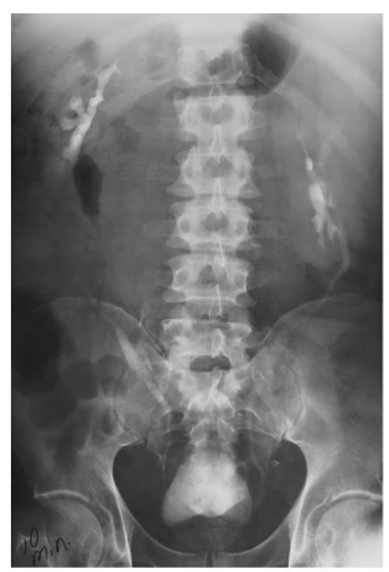

neurogenic bladder

papillary necrosis